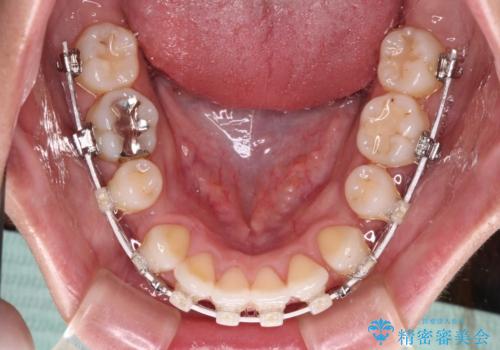

- 矯正装置

- 審美装置

- くちばしのような前歯の突出感を気にして来院された患者様です。

上下左右第一小臼歯4本を抜歯して、積極的に口元を引っ込めるよう、ワイヤー装置にて矯正治療を行うこととしました。